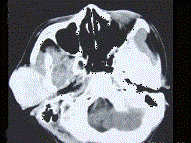

问题 19岁,女性患者,右侧面颊部肿胀一年,CT检查如图所示,请选择最佳答案 ( )

选项 A、右颊部横纹肌肉瘤 B、右颊部血肿 C、右颊部血管瘤 D、右颊部脂肪瘤 E、右颊部神经纤维瘤

答案 C